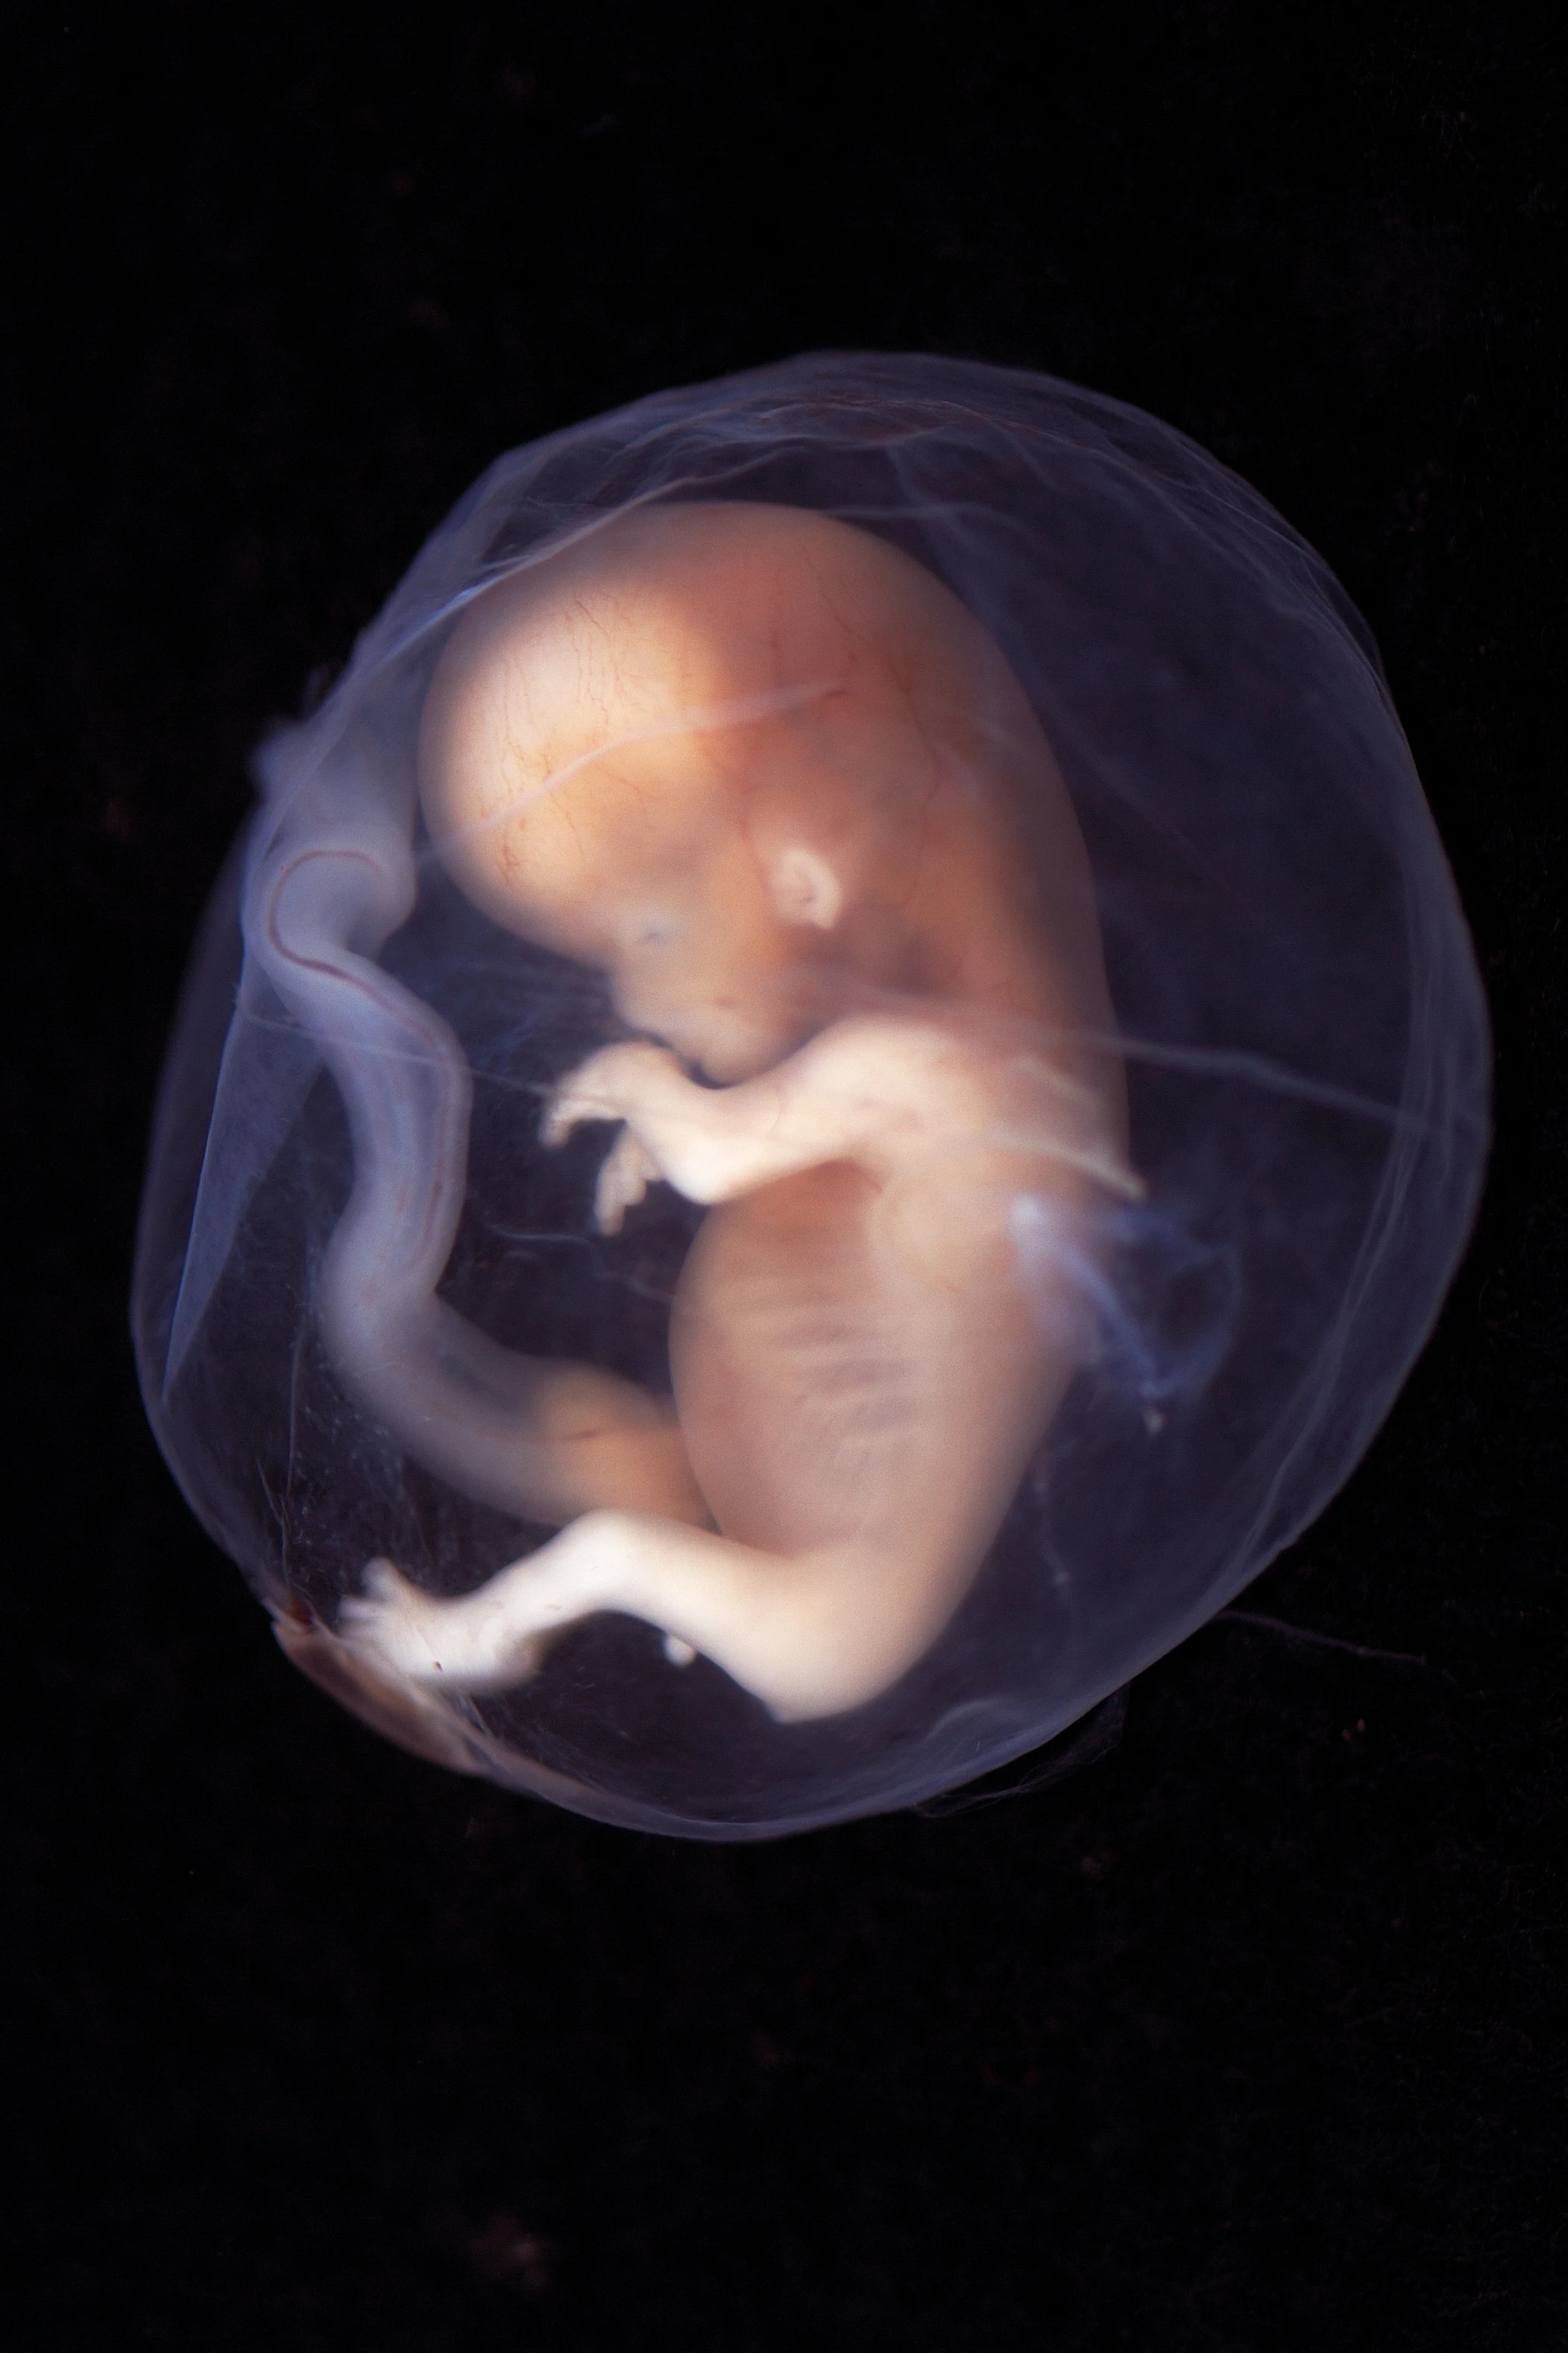

Беременность 6 Недель Развитие Фото

Беременность 6 Недель Развитие Фото 108 фотографий